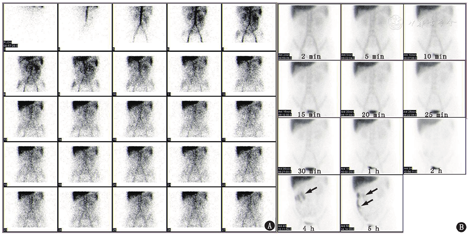

明确诊断PLE的必要条件是证实蛋白质从胃肠道丢失。蛋白质从胃肠道丢失的病理机制主要有3种:(1)胃肠道黏膜损伤,可以导致富含蛋白质的体液渗出;(2)炎性反应、浸润性和遗传性疾病使胃肠道的黏膜通透性增加,可导致蛋白质漏入肠腔内;(3)淋巴管阻塞、淋巴系统先天性异常或中心静脉压升高的疾病可导致淋巴管压力升高,从而使淋巴液从肠道丢失。为进一步明确PLE的诊断及鉴别蛋白质丢失的机制,患者行99Tcm-人血清白蛋白(human serum albumin, HSA)肠道蛋白丢失显像(图1)和99Tcm-硫化锑(antimony sulfide, ASC)淋巴显像(图2)。99Tcm-HSA肠道蛋白丢失显像中,血流期可见腹部显像剂摄取增高,以中上腹部为著,提示可能是腹部肠管血流灌注增加所致;之后的各期延迟显像见4 h(相当于第4组小肠部位)有异常放射性增高区,随时间延长放射性增高区逐渐移行,至5 h见升结肠显影。这个检查证实了肠道蛋白丢失,并且丢失的部位很可能位于第4组小肠。99Tcm-ASC下肢淋巴显像可见双下肢淋巴管显影清晰,回流通畅,腘窝、腹股沟、髂及腰干淋巴结显影清晰,各期显像腹部始终未见异常放射性增高区,因此排除了淋巴系统异常、淋巴液丢失所致的PLE。

如前所述,PLE的病理机制之一是蛋白质经淋巴液从肠道丢失。核素淋巴显像是了解淋巴系统走向、淋巴结形态和摄取胶体颗粒功能的核素显像技术。99Tcm-ASC下肢淋巴结显像可反映下肢、腹部、胸部淋巴系统有无异常,对于PLE患者可以观察腹部有无淋巴液渗漏,也可以为PLE的诊断以及病因提供相应依据(图4)。本例患者淋巴显像阴性,提示该患者的PLE并非经淋巴液丢失,而是其他原因导致。